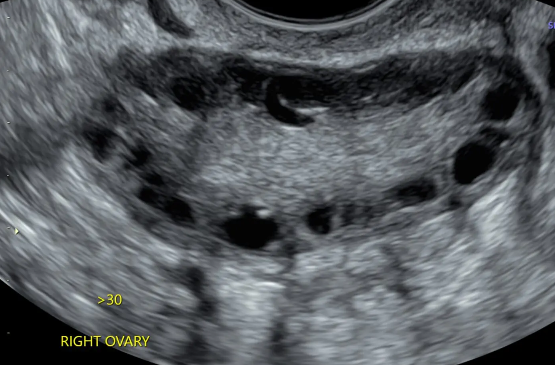

PCOS Differentials and Lab Test Interpretation

Irregular Periods? Here’s the High-Yield Workup That Saves Time